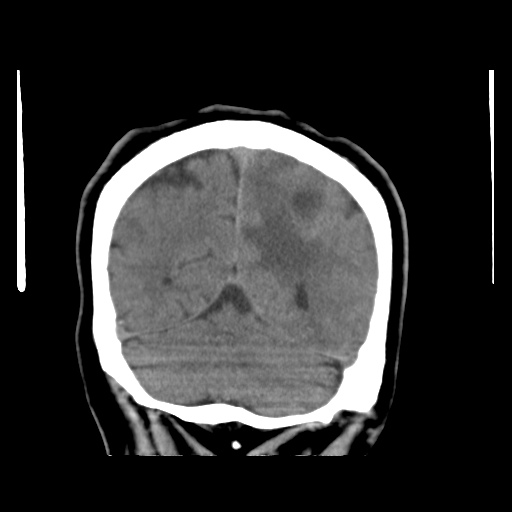

Caso neurorradiología

Paciente de 60 años con cuadro de 1 semana de evolución consistente en tropiezos frecuentes y alteración en la movilidad del miembro

inferior derecho. No refiere

cefalea u otros síntomas asociados, no pérdida de peso, no náuseas o emesis, no

sudoración nocturna. Antecedentes de hipertensión arterial y diabetes.

Resonancia magnética

Escanografía